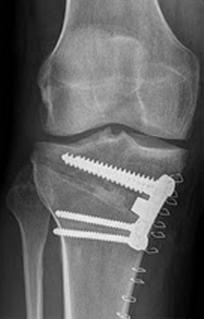

Knock Knees, also known as genu varum, is a condition where the legs appear bowed outwards when standing. This condition can cause discomfort, pain, and even difficulty walking. In severe cases, surgery may be required to correct the alignment of the legs. In this article, we will discuss the causes, symptoms, and treatment options for Knock Knees, including the various surgical procedures available.

The treatment options for knock knees will depend on the severity of the condition and the underlying cause. Some common treatments include

A doctor can diagnose knock knees by performing a physical examination and assessing the alignment of the legs. Imaging tests such as X-rays or MRI scans may also be used to confirm the diagnosis.